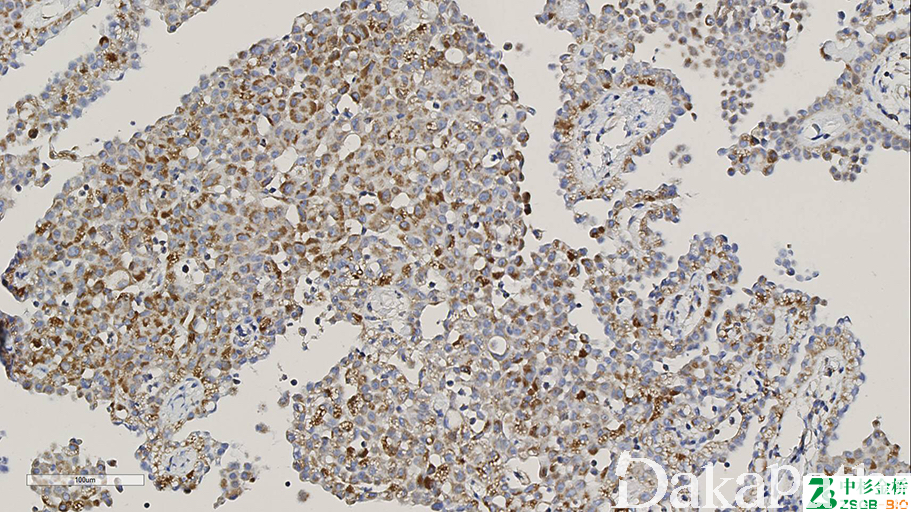

正常细胞普遍核表达 SDHB,异常表达缺失。

信号定位: 胞浆